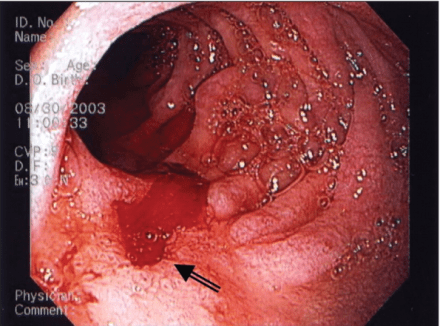

- Endoscopy

- Up to 90% sensitivity in identifying ulcer

- Next step if any red flags

- Malignant features requiring biopsy:

- Ulcerated mass protruding from lumen

- Nodular, clubbed, or fused folds

- Overhanging, irregular, or thickened ulcer margins